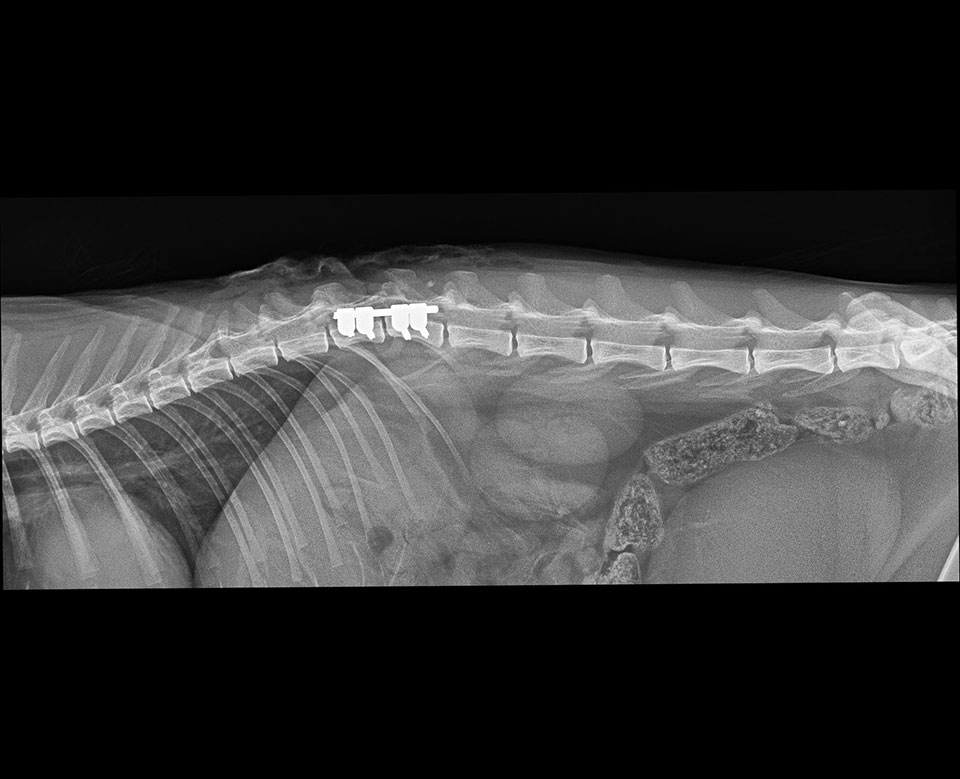

Mini SOP-LC (for 2,0mm srews) were used for stabilisation of vertebral luxation and fracture in cat.